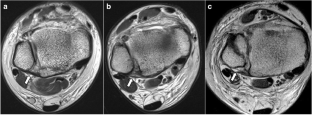

Fig. 2